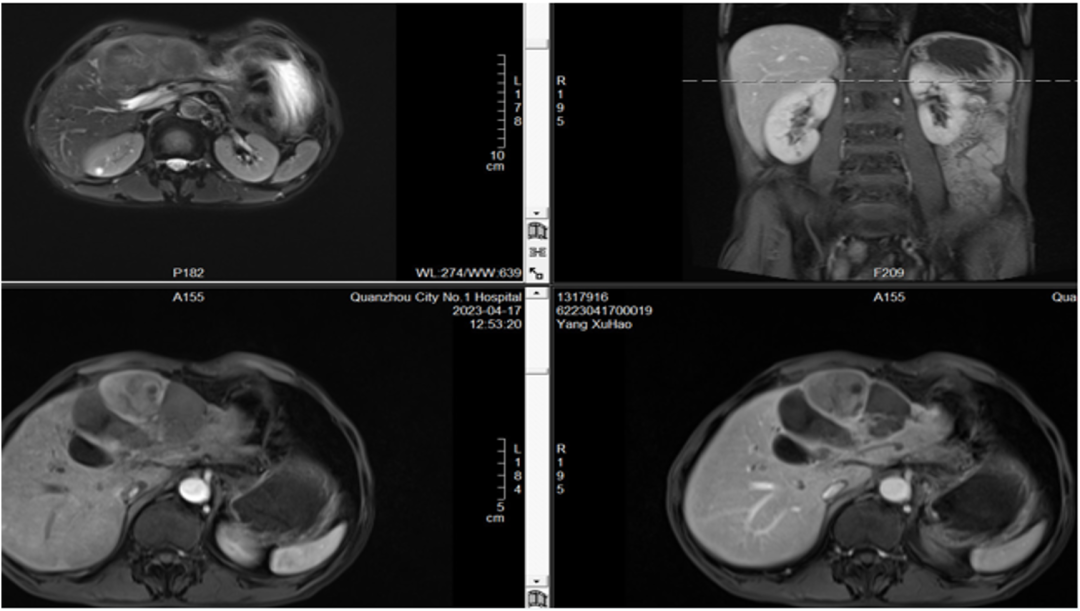

2023-04-17复查肝脏增强MRI(靶免11周期后):肿瘤强化病灶相仿,疗效评估:PR。

治疗经过5

2023-04-20,局麻下行TACE术。